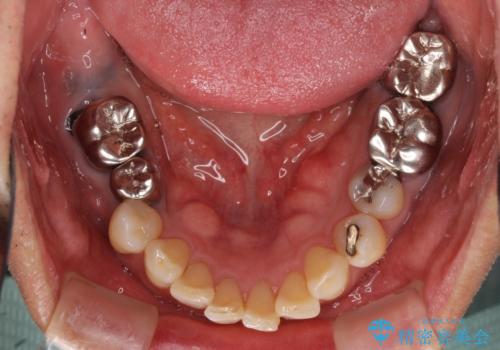

部分矯正を併用した奥歯のインプラント補綴治療

- 奥歯を他院で抜歯した後、インプラント治療を希望とのことで来院された患者様です。

ブリッジの支台を抜歯したことで2本のインプラントが必要であり、その後方はインプラント埋入に必要な骨量が不足していたため、上顎洞粘膜の挙上を行うこととしました。

また、残っている最後方歯は手前に倒れてきていたため、部分矯正により奥に移動させてから、インプラント埋入を行うこととしました。

部分矯正期間中はアンカースクリューやフック、ゴムなどが粘膜にあたり、大変な思いをすることになりましたが、そのおかげでインプラント補綴した歯と最後方歯の位置が非常に良好となり、まるでご自身の歯のように咬むことができるようになりました。